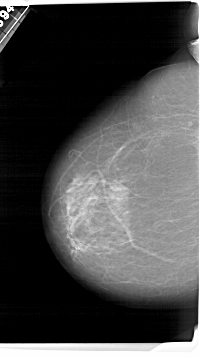

A_1495_1.LEFT_CC

LEFT_CC LINES 6796 PIXELS_PER_LINE 3796 BITS_PER_PIXEL 12 RESOLUTION 43.5 NON_OVERLAY